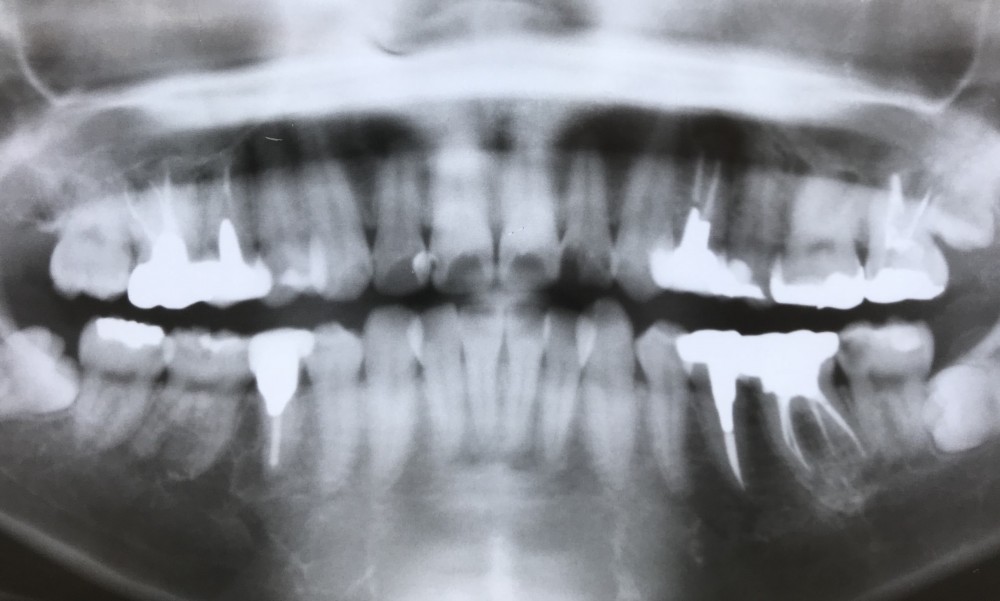

こちらが術前のパノラマ写真です。